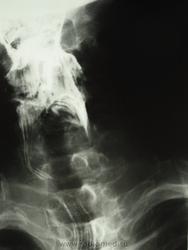

мужчина 1932 г.р. (лежачий пациент, инвалид) привезли со скорой на рентфию ОГК. случайно оказалась рядом и выяснила у сына, что он 3 дня не разговаривает и не кушает. Решила дать глоток бария пока лежит(снимки наспине), вот что получилось....

Образование или инородное тело?

С учетом таких контуров образования возможно лейомиома, но расположение странное, а может образование идет со стороны щитовидной железы?

наверно инородное тело врядли (большое какое то), может из щитовидки что то прорасло??? а может вообще заглоточный абсцесс????

Ну, у стариков инородное тело (кусок мяса) может дать интересные картинки.

Тоже на все 100% соглашаюсь с Валентином Львовичем, в первую очередь необходимо исключать т.н. "мясной завал", а мясо там...сало ...или еще что - дело десятое.....